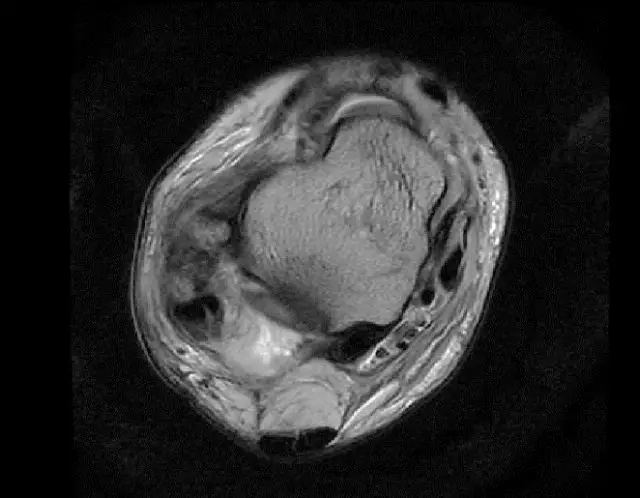

此片可以看到距腓前韧带和跟绯韧带有高信号大片的渗出病变,韧带结构松弛,增粗,这个地方可以看到腓骨前韧带的segond骨折块,所以考虑是踝关节外侧副韧带损伤,腓骨腱的segond骨折。